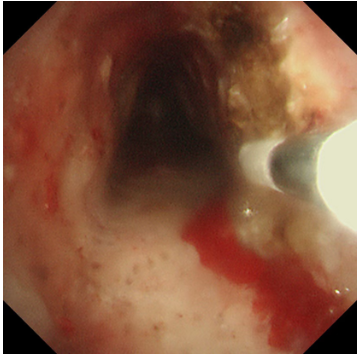

激光灼蝕,精準(zhǔn)“開路”:在氣管鏡引導(dǎo)下,首先利用高頻激光對(duì)堵塞氣道的增生組織進(jìn)行精準(zhǔn)、迅速地汽化切割。激光如同一位技藝高超的“雕刻師”,快速清除掉大部分梗阻物,為后續(xù)治療打開一個(gè)通暢的“窗口”,迅速緩解患者的窒息風(fēng)險(xiǎn)。

冷凍修復(fù),深度“清創(chuàng)”:隨后,應(yīng)用冷凍探頭對(duì)殘余的增生組織及基底進(jìn)行凍融治療。極低溫的探頭接觸組織,能使其變性、壞死并最終脫落,同時(shí)還能有效止血、減少瘢痕形成。這一步驟如同為氣道進(jìn)行一次深度的“保養(yǎng)與清潔”,能更徹底地清除病灶,降低復(fù)發(fā)風(fēng)險(xiǎn)。